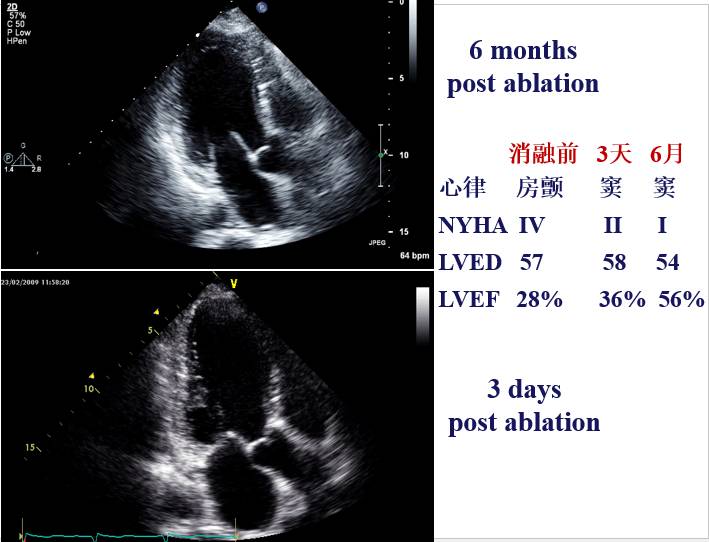

55F CAF 4 years ,CHF 6 months,NYHA III

LVED:58mm EF:28%

Ablations: PVIs 、 Roof、MI、CTI (2C3L)

6 Months Post Ablation